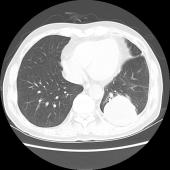

[影像描述]

左肺下叶可见高密度肿块影,边界清晰,边缘不规则,左肺下叶支气管局部截断,增强后病灶边缘轻度强化,中心未见明显强化;左侧胸腔内可见液性密度影;纵隔内未见明确肿大淋巴结影。